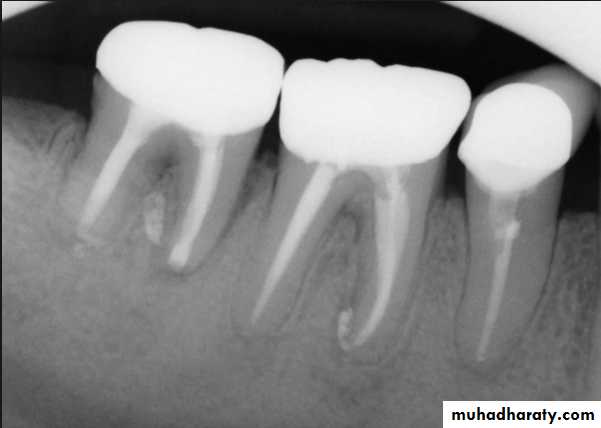

Evaluation of radiographic survey

All prospective abutment teeth must be critically evaluated4/2/2018

Root size, length and form

Teeth with large or long roots - Greater periodontal supportTapered or conical roots- un favorable

Multi rooted teeth with divergent roots are stronger abutment teeth than single rooted, multi rooted teeth with fused roots.4/2/2018

Signs of positive bone factor

A supportive trabecular patternHeavy cortical layer

Dense lamina dura

Normal bone height

Normal periodontal ligament space.

If retrograde bone changes occur, the patient has a negative bone factor ; prognosis is poor.